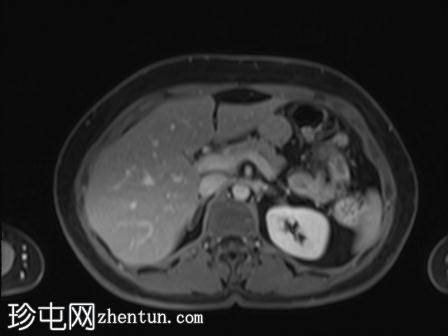

MRI

矢状位

T2加权像

可见局部晚期浸润性内生型宫颈癌,肿瘤大小为30 x 32 x 48 mm。该肿瘤已侵犯宫颈前唇和后唇的深层间质,以及子宫肌层的下段。

此外,肿瘤还累及宫旁组织。影像学检查发现异常淋巴结肿大,最大短轴直径(SAD)为10 mm,位于髂总血管分叉处和髂内动脉链下方。该淋巴结肿大在弥散加权成像(DWI)上显示水限制,且增强扫描后可见强化。

宫内节育器(IUD)位于子宫内正常位置。左侧子宫底壁内肌瘤大小为15 x 16 mm(FIGO 4期)。子宫内膜厚度约为3 mm,未见宫腔内病变。双侧卵巢外观正常,未见实性或囊性病变。